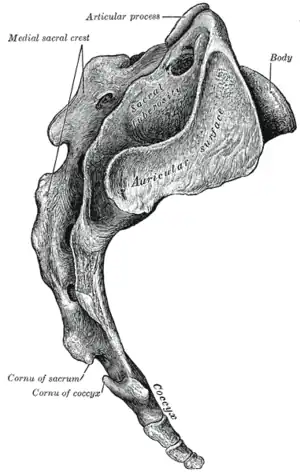

Hueso sacro, vista lateral. | ||

Imagen de la pelvis femenina, vista anterior. Cara lateral del sacro y coxis.

Cara lateral del sacro y coxis. Base del sacro.